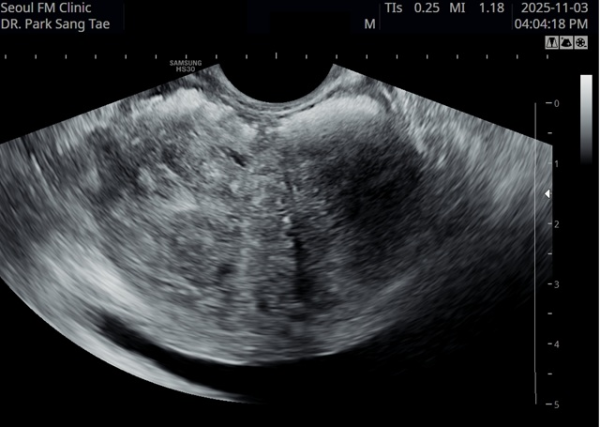

17개월동안 상급 의료 기관에서 전립선 치료에 대한 투약을 했으나 증상의 호전이 없이 배뇨장애와 배뇨시 통증으로

내원 당일 경직장 전립선 초음파 사진상 전립선내 거대 농양이 관찰되는 자료입니다.

"A transrectal prostate ultrasound image taken on the day of the visit, showing a large prostatic abscess in a patient

who had been receiving prostate treatment with medication at a higher-tier medical institution for 17 months without symptomatic improvement,

experiencing voiding dysfunction and pain during urination."